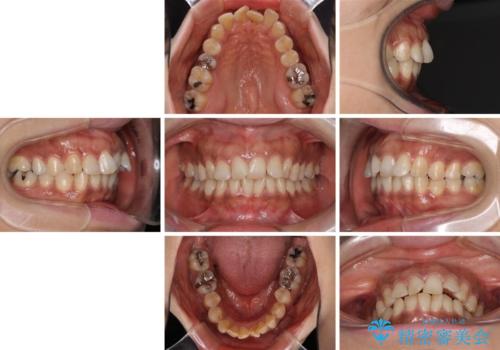

- 上下前歯のデコボコ改善をインビザラインにて行いたいとのことで来院された患者様です。

インビザラインをご希望のことで、IPR(歯と歯の間を削る)などによりスペースを獲得して、排列していくこととしました。

骨格的に上下顎が左右にずれていたため、正中位置は現状を維持したまま歯列不正を解消していくことになります。